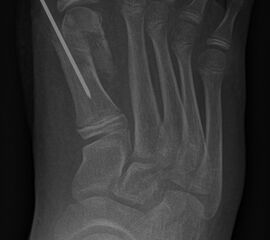

Zusätzlich schränken Wachstumsfugen die Wahl der Osteosynthese ein. Eine die Fuge kreuzende Osteosynthese ist ausschließlich mit Kirschner-Drähten möglich (Abb. 3).

Abb. 3 a-j: Beispiel einer Calcaneusverschiebeosteotomie mit offenen Wachstumsfugen und der entsprechenden Osteosynthese mit Kirschner Drähten. Lokalisation der Osteotomie (a), Lage der Fräse (b-d), Drahtlage mehrere Ansichten (e-h), Heilung der Osteotomie 4 Wochen postoperativ und Entfernung der Drähte (i-j).

Zum Lesen der Bildbeschreibung und zur Vollansicht bitte die Bilder anklicken. Bilder: A. Helmers.

Calcaneus-Osteotomie

Die minimalinvasive Calcaneusverschiebeosteotomie bietet eindeutige Vorteile gegenüber dem offenen Verfahren, sodass wir bei Kindern und Jugendlichen nahezu keine offene Verschiebeosteotomie mehr durchführen. Am Calcaneus liegt die offene Wachstumsfuge dorsal. Bei der Durchführung müssen Schenkel der V-förmigen Osteotomie daher etwas steiler angelegt werden, in einem stumpfen Winkel (siehe Abb. 3 a-j). Für die Osteotomie liegen unsere Patienten auf dem Rücken und der BV wird für die exakte Seitaufnahme eingestellt. Der Fuß lagert auf einem hohen OP-Kissen und die Osteotomie kann bequem mit einem langen Kirschner-Draht und einem sterilen Stift angezeichnet werden (Abb. 15).